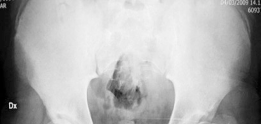

Revision THA Acetabulum Paprosky Type IIIA. ARMD with Metallosis with Severe Periacetabular Osteolysis and Co…

Case Title: Acetabular Impaction Grafting Demographics Age: 78 Sex: female BMI: 28 Relevant Past Medical Hist…